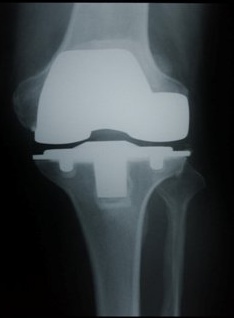

인공관절 수술이란 심하게 닳아 없어져 버린 연골 대신에 인체친화적인 재료로 만들어진 튼튼한 관절 연골로 이상이 있는 부분에 인공적으로 보강을 해주는 수술을 말한다. 수술을 받게 되면 통증이 크게 경감되며 일상생활에 전혀 지장이 없게 해준다. 그러나 과거에는 나이든 어르신들에게 인공관절 수술이란 두려움의 대상이었기 때문에 인공관절 수술률이 저조 했었던 것이 사실이다. 그러나 이제는 시간의 흐름에 따라 수술기술이 비약적인 발달을 하였기 때문에 인공관절 수술을 그리 걱정할 필요는 없겠다.

금천구에 위치한 관절전문 희명병원(이사장 최백희) 정형외과 김정민 진료부장은 “과거에는 잘못된 인식으로 인하여 수술을 망설이는 환자분들이 많았던 이 사실입니다. 그러나 저희 희명병원에서는 인공관절 수술에 있어서 전문병원으로 인공관절 수술이 90세 이후에도 시행되고 있으며 성공한 사례가 많아 고령의 환자분들 수술에 적합한 병원입니다. 특히 희명병원에서 인공관절수술 전문팀이 상주하고 있으며 최소 절개법으로 30분 이내에 수술이 가능하며 수술 후에도 좋은 예후를 위하여 집중치료와 통증관리로 인한 재활치료까지 시행되고 있습니다”라며 희명병원의 인공관절 수술시스템에 대하여 설명했다.

이렇듯 인공관절 수술 전문 희명병원에서는 풍부한 경험과 검증된 실력으로 똘똘 뭉친 전문 의료진들에 의해서 최신 의료기구와 최첨단 치료기법을 사용하여 퇴행성 관절염의 완치를 위한 인공관절 수술이 진행 되고 있다.